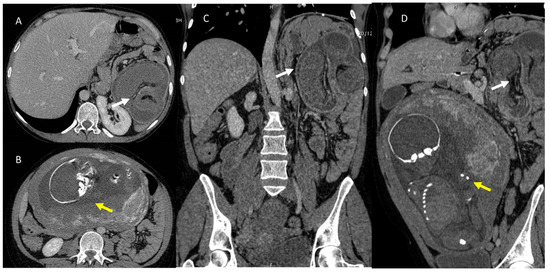

In modern clinical practice, there is an increasing dependence on imaging techniques in several settings, and especially during emergencies. Consequently, there has been an increase in the frequency of imaging examinations and thus also an increased risk of radiation exposure. In this context, a critical phase is a woman’s pregnancy management that requires a proper diagnostic assessment to reduce radiation risk to the fetus and mother. The risk is greatest during the first phases of pregnancy at the time of organogenesis. Therefore, the principles of radiation protection should guide the multidisciplinary team. Although diagnostic tools that do not employ ionizing radiation, such as ultrasound (US) and magnetic resonance imaging (MRI) should be preferred, in several settings as polytrauma, computed tomography (CT) nonetheless remains the examination to perform, beyond the fetus risk. In addition, protocol optimization, using dose-limiting protocols and avoiding multiple acquisitions, is a critical point that makes it possible to reduce risks. The purpose of this review is to provide a critical evaluation of emergency conditions, e.g., abdominal pain and trauma, considering the different diagnostic tools that should be used as study protocols in order to control the dose to the pregnant woman and fetus. Full article

Show Figures

Figure 1